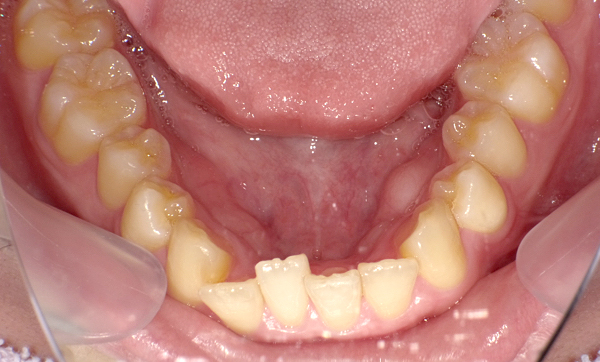

症例_009 「上下の前歯」症例

治療期間:7ヶ月金額:54万円+税20代女性捻転歯一部の反対咬合前歯のガタガタ